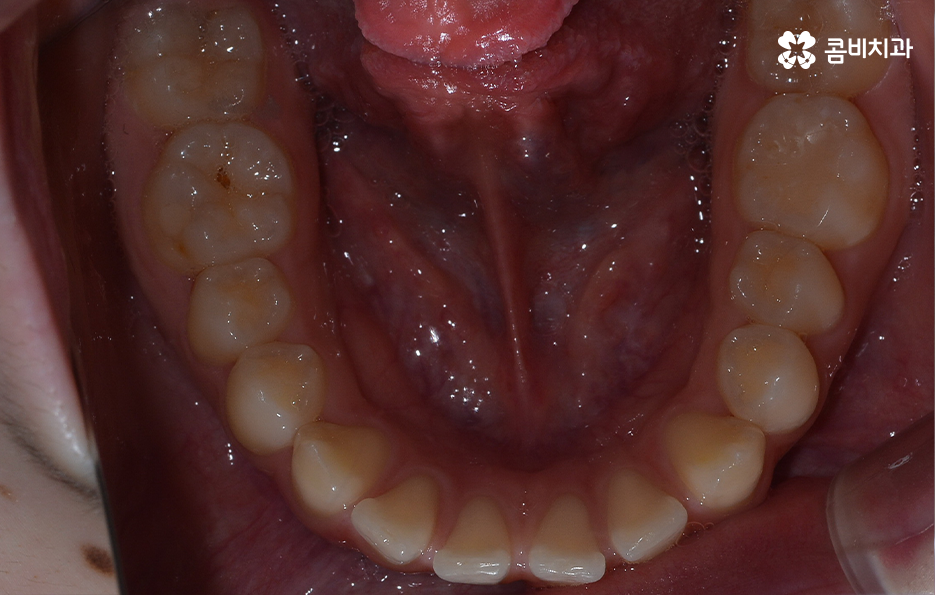

오늘 소개드릴 케이스의 경우 아랫니가 비교적 작기 때문에 교정을 통해 모아주고 윗니의 경우 측면으로 볼 때 더 잘 느껴지겠지만 다소 돌출된 상태이기 때문에 윗니는 발치를 통해 치아 이동 공간을 확보하여 돌출된 앞니를 안쪽으로 모아준 사례로 볼 수 있는데요

아랫니의 경우 치아 사이가 벌어져 있기 때문에 치아를 이동시킬 수 있는 공간이 이미 확보된 상태이고 윗니는 다소 돌출된 앞니를 안쪽으로 들어오게 하면서 심미선을 얼굴형에 조화롭게 맞출 수 있으며 그와 동시에 윗니와 아랫니의 교합도 고려한 치료 계획을 세운 것으로 간단하게 말씀드릴 수 있어요

사진으로 보더라도 아랫니 사이가 눈에 띄게 벌어져 있는 것을 확인할 수 있어요. 보통 웃을 때는 윗니 위주로 보이긴 하지만 아랫니가 이정도로 벌어져 있는 경우에는 콤플렉스로 여겨질 수 있어요